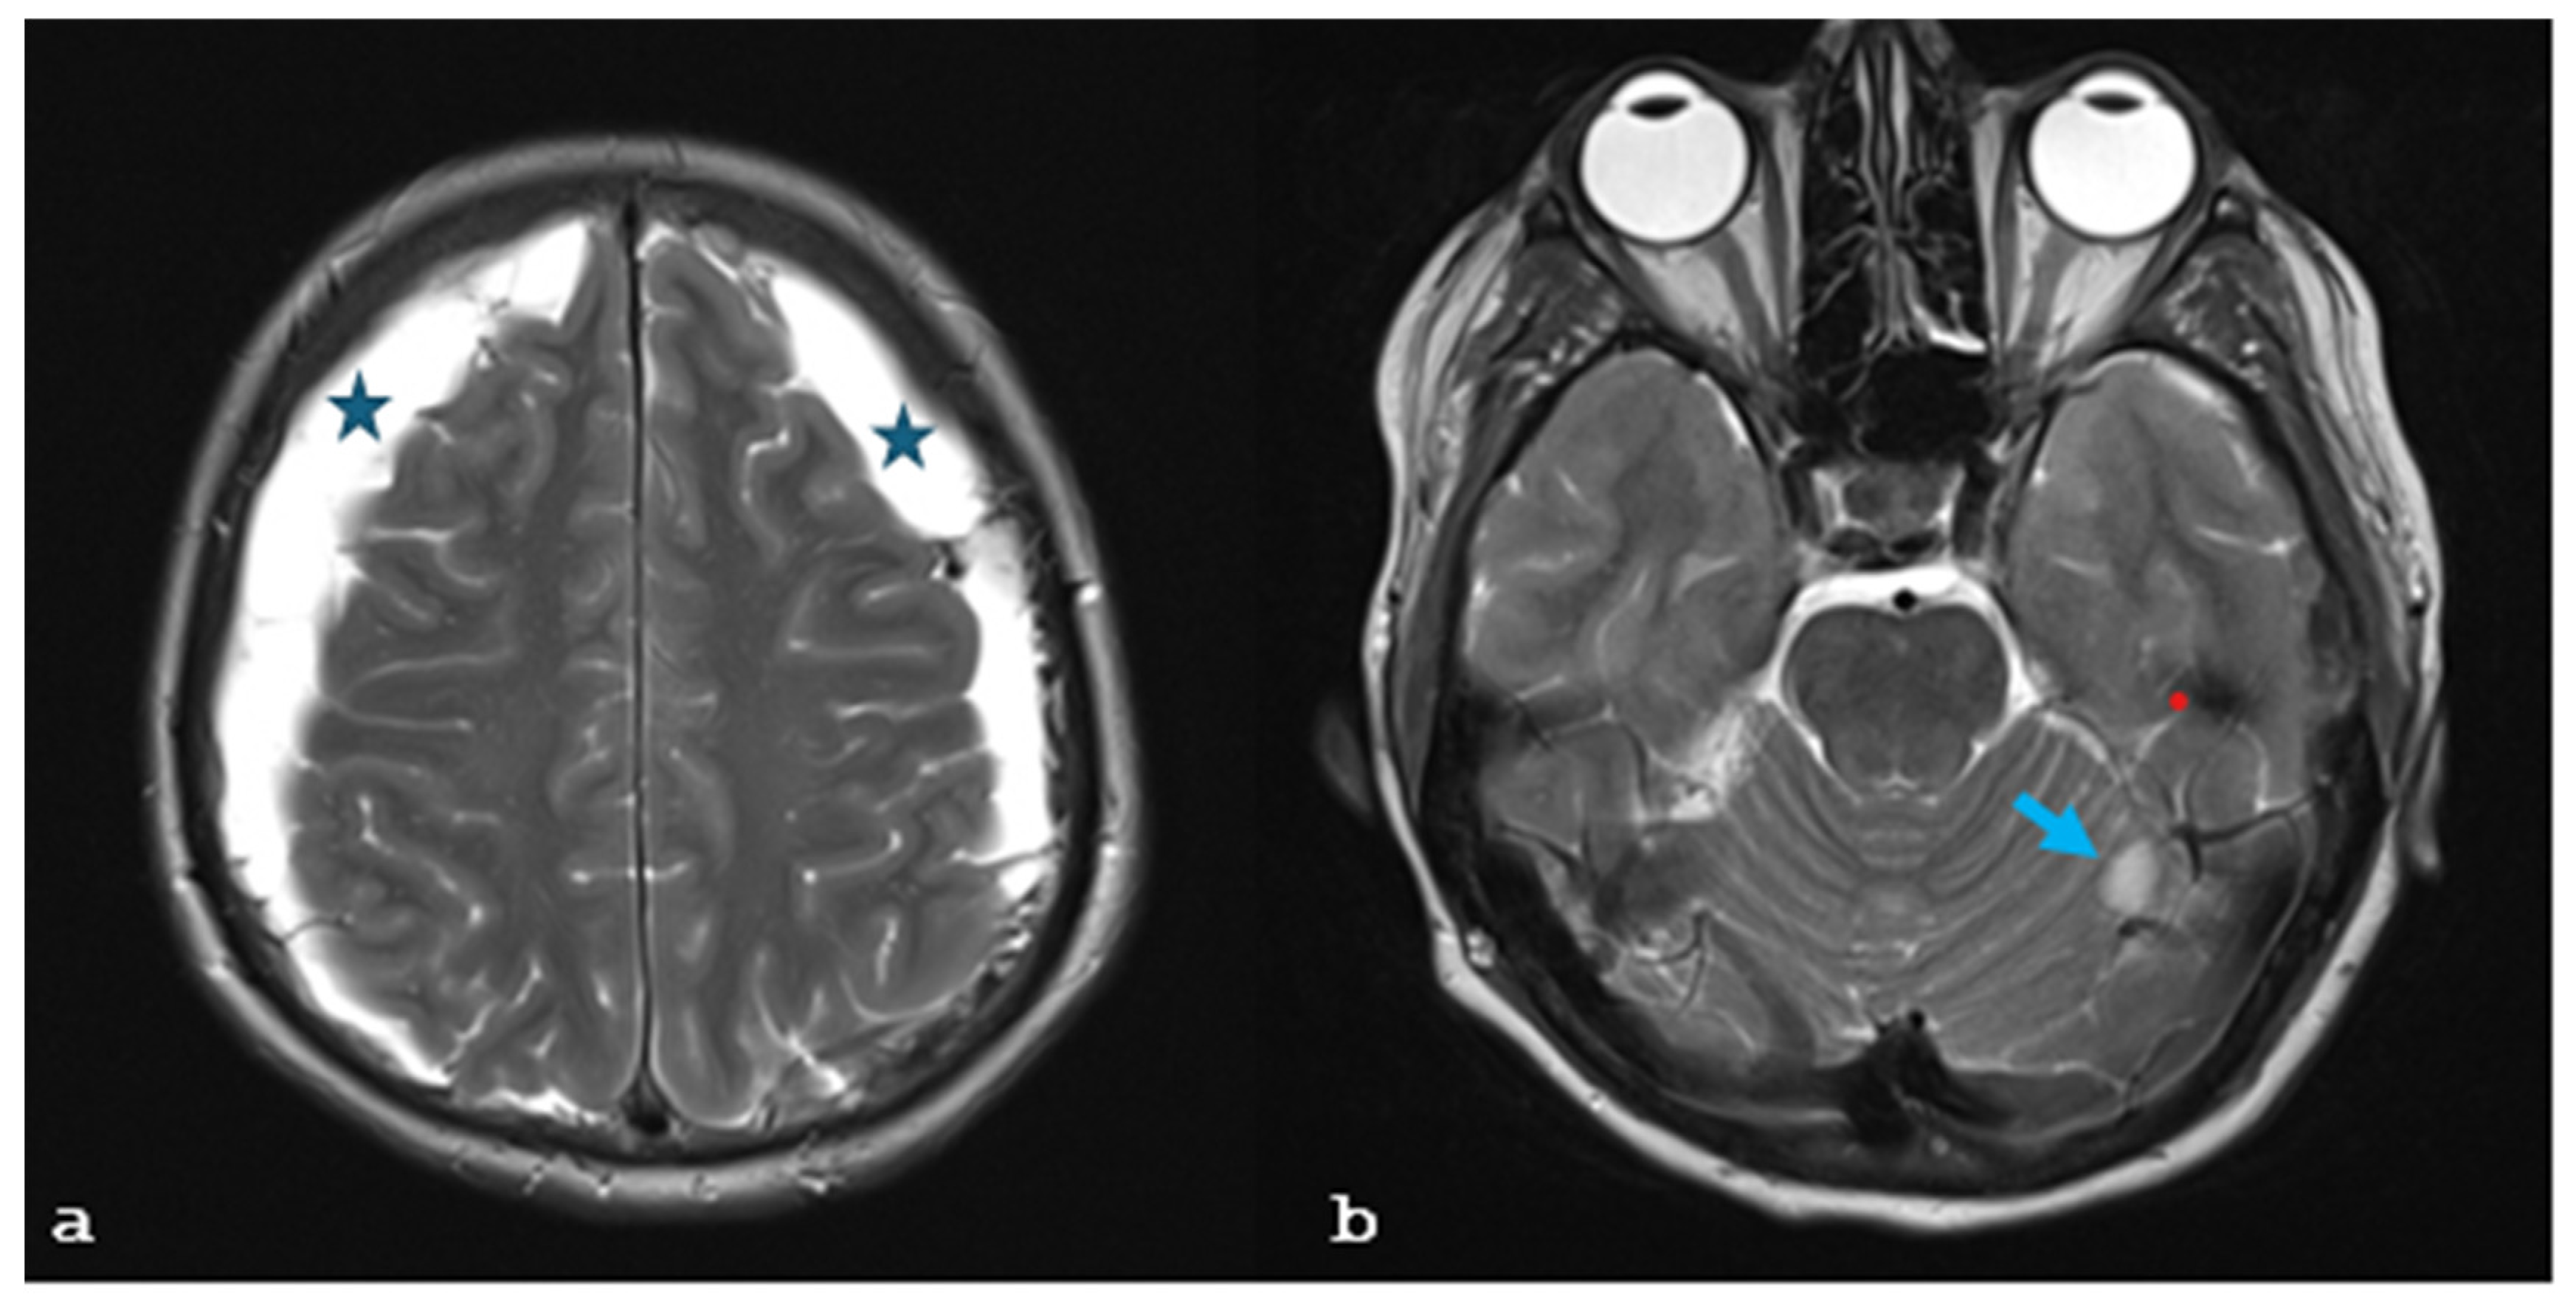

2. Case Report